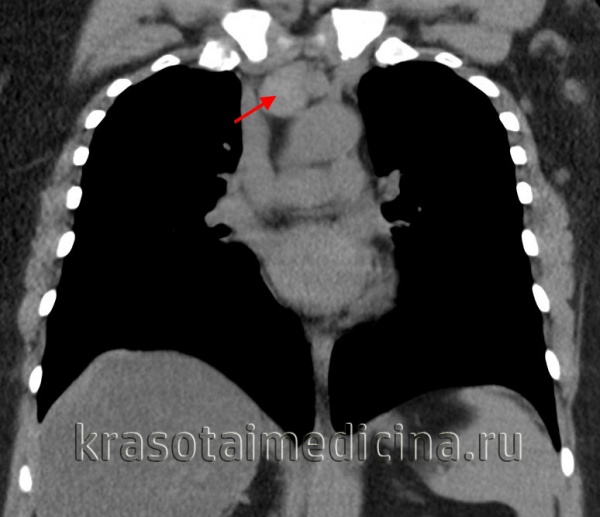

КТ, МРТ при неходжкинской лимфоме лимфоузлов поднижнечелюстного пространства

• Неходжкинская лимфома = злокачественная опухоль лимфоретикулярной системы, которая предположительно происходит из лимфоцитов и их производныхб) Визуализация:

1. Общая характеристика:

• Лучший диагностический критерий:

о Множественные двусторонние увеличенные лимфоузлы сразу в нескольких цепях

• Локализация:

о Может быть поражена любая цепь, в том числе I уровня

• Размер:

о Обычно несколько узлов размерами 1-3 см

о Крупный доминирующий узел может достигать 3-5 см

• Морфология:

о Лимфоузлы округлые или овальные, обычно солидные2. КТ при неходжкинской лимфоме лимфоузлов поднижнечелюстного пространства:

- Могут быть изоинтенсивны мышцам, могут эффективно накапливать контраст3. МРТ при неходжкинской лимфоме лимфоузлов поднижнечелюстного пространства:

• Т1ВИ:

о Изоинтенсивны мышце

• Т2ВИ:

о Изо- или гиперинтенсивны мышце

• Т1ВИ с КУ:

о Умеренное однородное накопление контраста

о При некрозе накапливают контраст по периферии4. Рекомендации по визуализации:

• Лучший метод визуализации:

о КТ с КУ-исследование первой линии

• Протокол исследования:

о В последнее время для оценки распространенности все чаще используют ПЭТ/КТв) Дифференциальная диагностика неходжкинской лимфомы лимфоузлов поднижнечелюстного пространства: